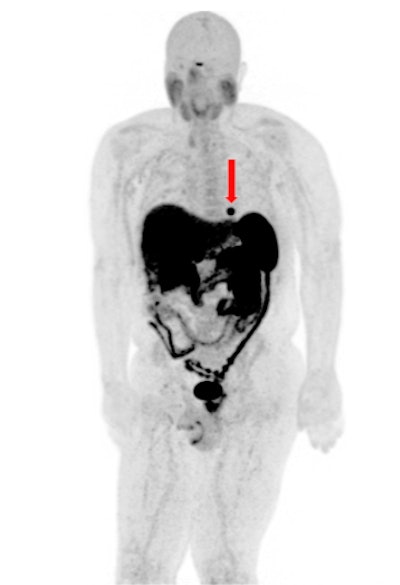

PET/CT has no rivals when it comes to the detection and surveillance of cardiac metastases in well-differentiated gastroenteropancreatic neuroendocrine tumors (GEP-NETs) as well as guiding clinical management, according to research presented at the annual congress of the European Association of Nuclear Medicine (EANM 2020).

"Chest CT demonstrates poor sensitivity for detection of cardiac metastasis, with cardiac MRI performing much better. Still, neither CT nor MRI is as sensitive as [gallium-68 (Ga-68)] DOTATATE PET/CT for detection of neuroendocrine cardiac metastasis," noted Dr. John Renfrew and colleagues from the Mayo Clinic in Phoenix, Arizona, U.S.

Evidence from the Mayo Clinic confirms that the prevalence of cardiac metastasis is associated with high tumor burden, and an average of 2.7 other organ systems are also involved when these metastases are seen. Further, patients typically demonstrate a Krenning score of 3-4 when they have cardiac metastases.

"While hepatic and nodal metastases are commonplace at the time of NET diagnosis, cardiac metastases are found much less frequently," explained Renfrew, who is a postgraduate year 5 (PGY-5) radiology resident. "The diagnostic criterion of cardiac metastasis is focal tracer uptake in the myocardium."

The group evaluated the prevalence, distribution pattern, and radiotracer uptake characteristics of cardiac metastasis on Ga-68 DOTATATE PET/CT. On PET images, they documented and analyzed the maximum standardized uptake value of the cardiac metastasis and left ventricular chamber (blood pool), the Krenning score of the cardiac metastasis, and the presence of multisystem metastasis. They performed correlation with diagnostic CT and/or cardiac MRI to confirm the location of metastasis in the heart.

Between October 2017 and March 2020, 1,426 Ga-68 DOTATATE PET/CT and PET/MRI scans were performed at the Mayo Clinic in Arizona. Twenty-six patients (mean age, 64 ± 10.17 years; male to female ratio of 11-to-10) were diagnosed with a cardiac metastasis, always with coexistence of multisystem metastases.

A total of 16 cardiac lesions were located in the left ventricle, eight were in the interventricular septum, and five were in the right ventricle.

The average SUVmax of these lesions was 9.2 (range, 2.6-24.1), and the Krenning score was 2-4. The average SUVmax of blood pool was 1.2 (range, 0.5-2.4). The average lesion to blood pool SUV ratio was 8.3 (range, 2.6-18.2).